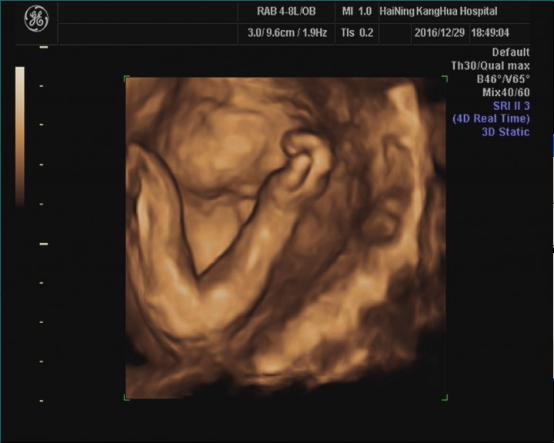

海宁康华医院“胎儿三维彩超检查”,为您创造“透视”条件!

胎儿三维超声检查最佳时间:

22—24周(备注:双胎不做三维超声检查)